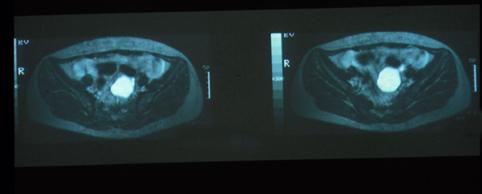

疾病(病理主体)的分类肿瘤样病变/异位粘膜

部位(按器官分)大肠/乙状结肠

检查方法MRI

肿瘤最大直径40以上